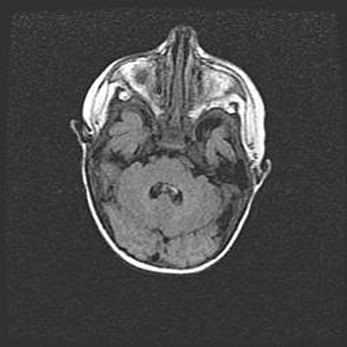

Церебральная ишемия II.

Возраст: 7 дней

Вес: 3350 г

Пол: женский

Окружность головы: 35 см

Срок гестации: 39 недель

Ишемия головного мозга – это состояние, которое развивается в ответ на кислородное голодание вследствие недостаточного мозгового кровообращения. У новорожденных она является следствием дефицита кислорода, что ведет к метаболическим расстройствам различной степени тяжести в тканях головного мозга, в том числе к развитию коагуляционных некрозов и гибели нейронов.